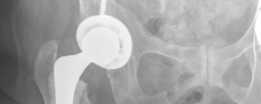

Once the appropriate size was reached, a highly porous, titanium-coated hemispherical cup was impacted into place. The target orientation was 40-45 degrees of inclination and 15-20 degrees of anteversion. Excellent primary stability was achieved via the equatorial press-fit. Two cancellous screws were placed in the postero-superior quadrant (the safe zone) to augment initial fixation. A highly cross-linked polyethylene liner was then impacted into the shell.

Following final stem cementation, the definitive femoral head (typically a 32mm or 36mm ceramic or cobalt-chrome head, depending on the cup size) was impacted onto the trunnion. The hip was reduced, and final stability checks were performed.